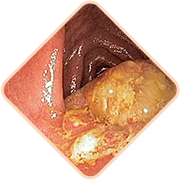

Az aranyér 3 halálosan veszélyes következménye, ha nem kezeli a problémát

Bármelyik a lent felsoroltak közül

a beteg hirtelen halálát okozhatja!

A széklet hatalmas mennyiségű mikrobát, baktériumot és gombát tartalmaz. Ha a fertőzés bejut a kismedencei szövetekbe és a szomszédos szervekbe, veszélyes gyulladás és vérmérgezés is lehetséges

Az aranyeres csomók megtelt erei nagyon gyengék. Gyakran szétszakadnak. A vérveszteség mértéke ebben az esetben olyan lehet, hogyvérátömlesztésre is sor kerülhet

Az erekbe vérrögök jöhetnek létre. Ezek a vérrögök leszakadhatnak a vénák falairól és elzárhatják a belső szervekhez vezető ereket, megzavarva így a vérkeringést, és elzárhatják a pulmonalis artériákat.Ebben az esetbne nagy a halál valószínűsége